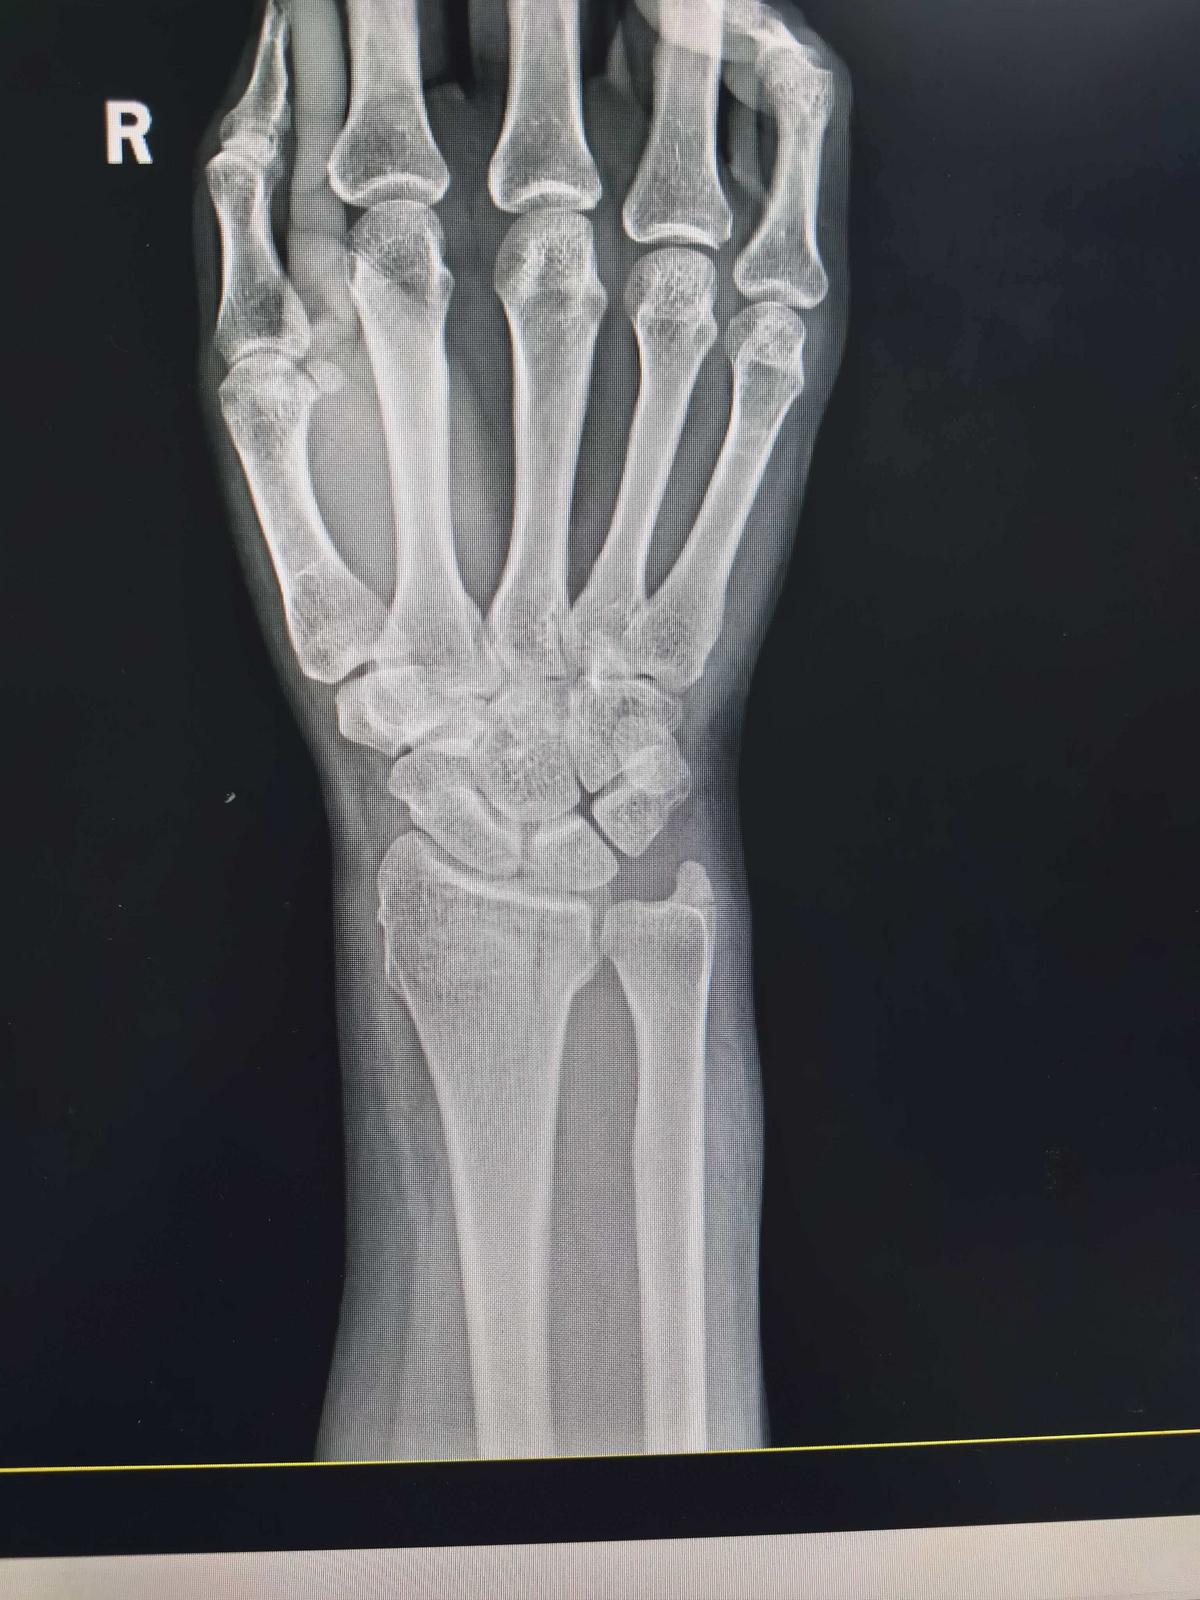

作为南通市区急救网络核心成员之一,南通市第三人民医院急诊科接诊量同步增加,截至当日上午,已接诊8名雪天路滑摔伤患者。其中71岁的李先生(化名)因摔倒致手指开放性骨折收治入院,58岁的赵女士(化名)摔倒后尺桡骨骨折。所幸,其余患者均为轻伤,经处理后病情平稳。

患者尺桡骨骨折